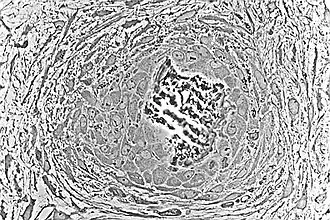

Embryologic mesenchymal cells (MSC) condense into layers of vascularized primitive connective tissue. Certain mesenchymal cells group together, usually near or around blood vessels, and differentiate into osteogenic cells which deposit bone matrix constitutively. These aggregates of bony matrix are called bone spicules. Separate mesenchymal cells differentiate into osteoblasts, which line up along the surface of the spicule and secrete more osteoid, which increases the size of the spicule.

As the spicules continue to grow, they fuse with adjacent spicules and this results in the formation of trabeculae. When osteoblasts become trapped in the matrix they secrete, they differentiate into osteocytes. Osteoblasts continue to line up on the surface which increases the size. As growth continues, trabeculae become interconnected and trabecular bone is formed. The term primary spongiosa is also used to refer to the initial trabecular network.